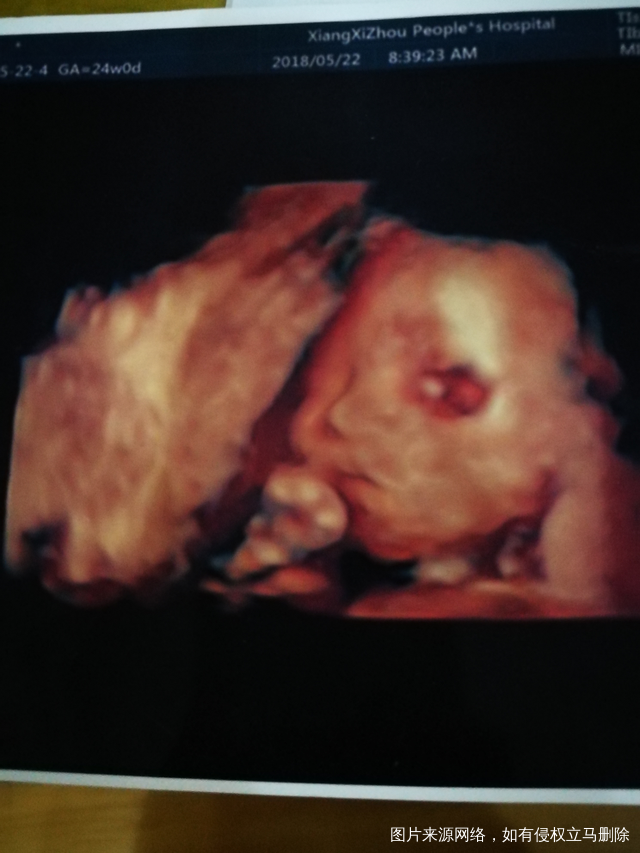

麻烦医生帮忙看看四维结果